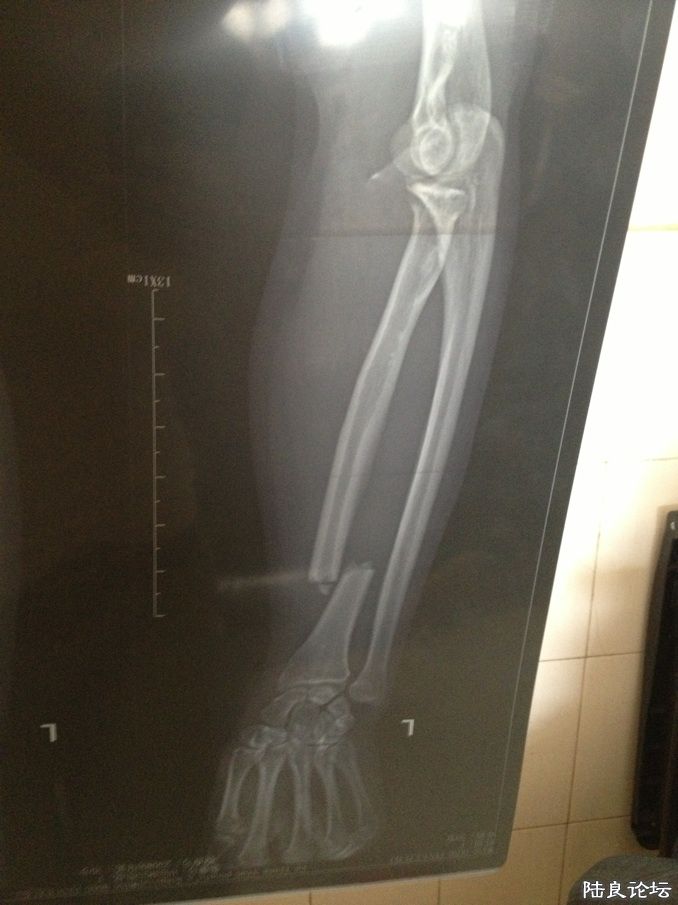

当时片子就显示骨折了